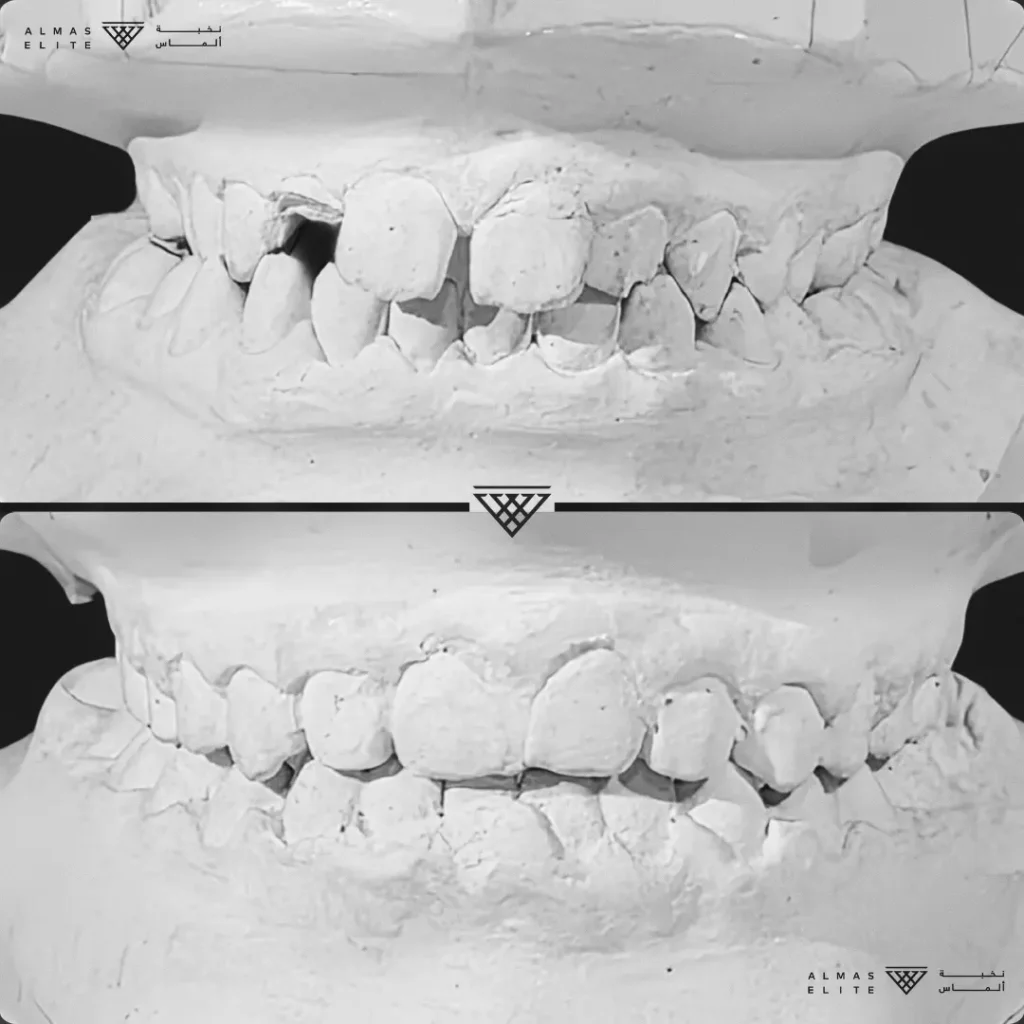

- تشخيص دقيق يشمل الأشعة والتحليل الرقمي للأسنان والفكين.

٢) التقييم والتشخيص الشامل

يشمل صور الأشعة والتحليل الرقمي للأسنان والفكين للوصول إلى تشخيص دقيق.

٣) وضع خطة علاجية مخصصة

تتضمن نوع الجهاز الأنسب، المدة المتوقعة، وتكلفة العلاج، مع شرح واضح لما يمكن توقعه أثناء رحلة التقويم.